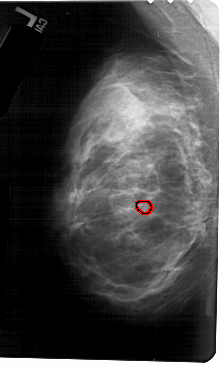

A_1685_1.RIGHT_CC

RIGHT_CC LINES 5491 PIXELS_PER_LINE 2956 BITS_PER_PIXEL 12 RESOLUTION 43.5 NON_OVERLAY

FILE: A_1685_1.LEFT_CC.OVERLAY

TOTAL_ABNORMALITIES 1

ABNORMALITY 1

LESION_TYPE CALCIFICATION TYPE PLEOMORPHIC DISTRIBUTION CLUSTERED

ASSESSMENT 4

SUBTLETY 1

PATHOLOGY BENIGN

TOTAL_OUTLINES 1

BOUNDARY